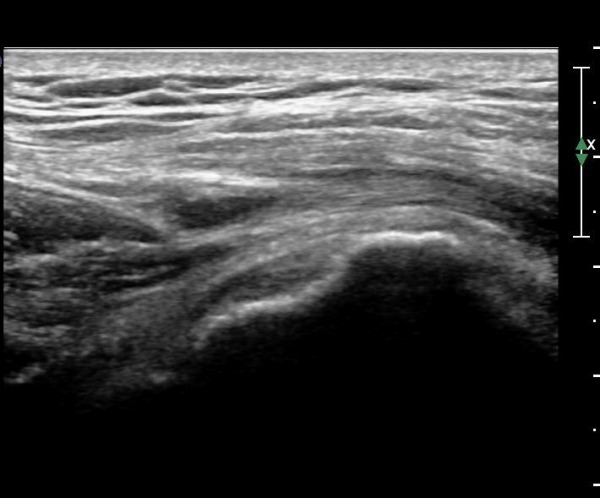

ÃÊÀ½ÆÄ °Ë»ç

´ëÀüÀÚ µÚÂÊ È¾´Ü¸é°Ë»ç¿¡¼­ ÁߵбÙÈûÁÙ°ú Àå°æÀÎ´ë »çÀÌ¿¡ ·®ÀÇ ¼ö¾×Àú·ù°¡ °üÂûµÇ°í(»çÁø 1)

ŽÃËÀÚ¸¦ ¸Ó¸®ÂÊÀ¸·Î À̵¿ÇÏ´Ï ¼ö¾×Àú·ù°¡ ´õ ¸¹ÀÌ °üÂûµÈ´Ù(»çÁø 2, 3).